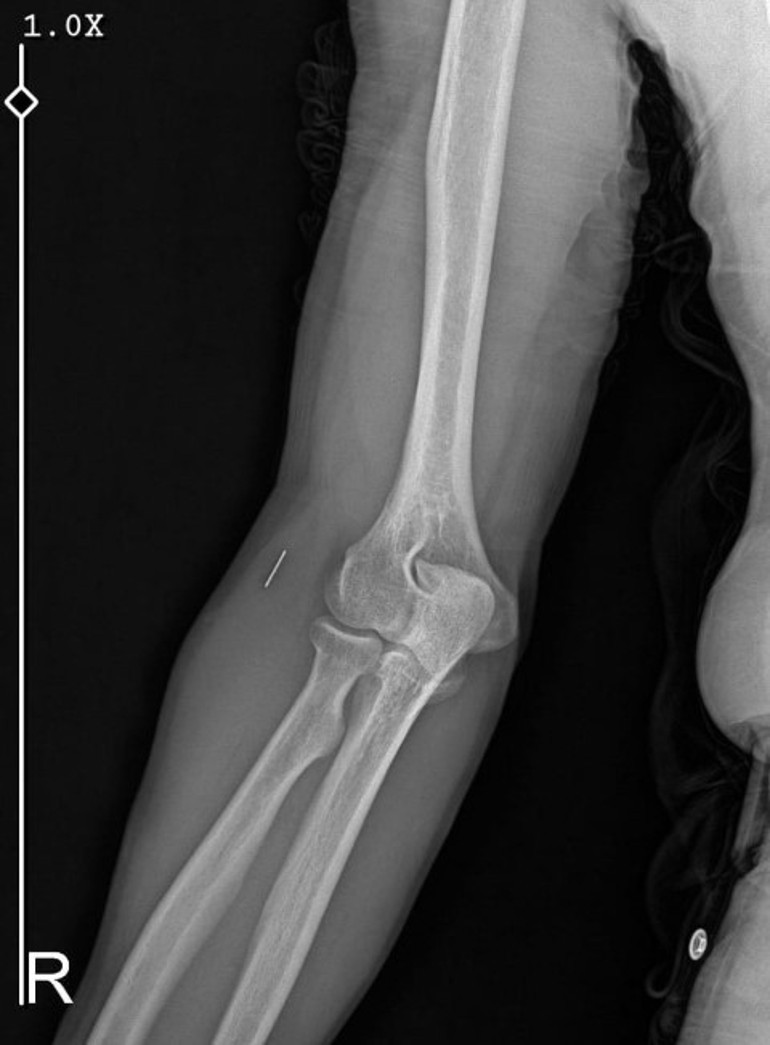

Öte yandan, ameliyatların ardından ağrıları devam eden Güleryüz'ün kolunda metal parça bulunduğu ve bu parçanın parmak bölgesinden dirseğe doğru ilerlediği öne sürüldü. Ayrıca, fabrikada temizlik personeli olarak çalışan Nurettin Güleryüz'ün hastane sürecinde işten çıkarıldığı da öğrenildi.